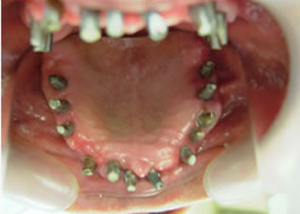

症例4 57歳女性

治療前

(下11本、上1本抜歯済み)

1.下11本、上1本抜歯、同時に総義歯セット